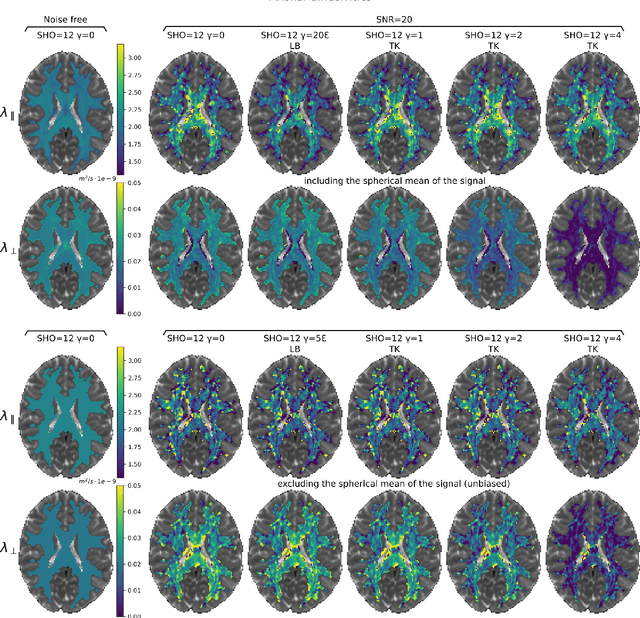

We enable the estimation of the per-axon axial diffusivity from single encoding, strongly diffusion-weighted, pulsed gradient spin echo data. Additionally, we improve the estimation of the per-axon radial diffusivity compared to estimates based on spherical averaging. The use of strong diffusion weightings in magnetic resonance imaging (MRI) allows to approximate the signal in white matter as the sum of the contributions from axons. At the same time, spherical averaging leads to a major simplification of the modeling by removing the need to explicitly account for the unknown orientation distribution of axons. However, the spherically averaged signal acquired at strong diffusion weightings is not sensitive to the axial diffusivity, which cannot therefore be estimated. After revising existing theory, we introduce a new general method for the estimation of both axonal diffusivities at strong diffusion weightings based on zonal harmonics modeling. We additionally show how this could lead to estimates that are free from partial volume bias with, for instance, gray matter. We test the method on publicly available data from the MGH Adult Diffusion Human Connectome project dataset. We report reference values of axonal diffusivities based on 34 subjects, and derive estimates of axonal radii. We address the estimation problem also from the angle of the required data preprocessing, the presence of biases related to modeling assumptions, current limitations, and future possibilities.